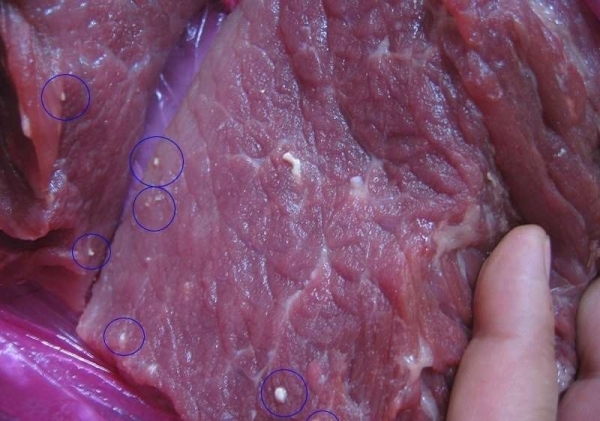

在醫生仔細詢問病患是否有吃到不整潔的食物以後,才發現到婷婷所屬的村落常常會在過年過節的時刻殺豬來慶祝,尤其每每總是把最嫩的肉放進酌料裡拌一拌生吃,這一吃讓婷婷吃了有10年之久。

其實當少量的寄生蟲吃進體內後,會被胃酸破壞殆盡,對人體沒有什麼危害情形發生。但假若是吃進了大量被絛蟲感染的豬肉,這些寄生蟲卵將會進入人體的腸道,在腸道發育成成蟲之後,就是人們常說的「絛蟲病」,尤其當一部分蟲卵在發育成幼蟲之後,繼而會進入腸壁,隨後進入血液、淋巴系統、肌肉等身體各個部位遊走感染。